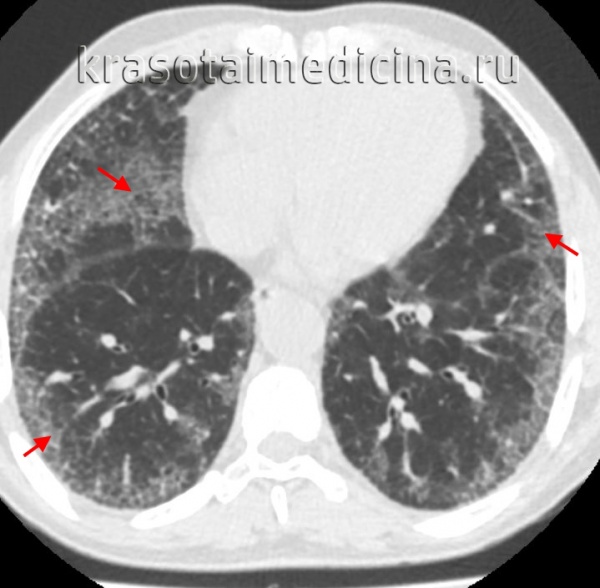

- КТ высокого разрешения. Помогает уточнить распространенность поражения легочной ткани, оценить стадию, активность и темпы прогрессирования фиброзного процесса.

КТ ОГК. Интерстициальная пневмония, участки «матового стекла» (красная стрелка) и ретикулярные изменения.